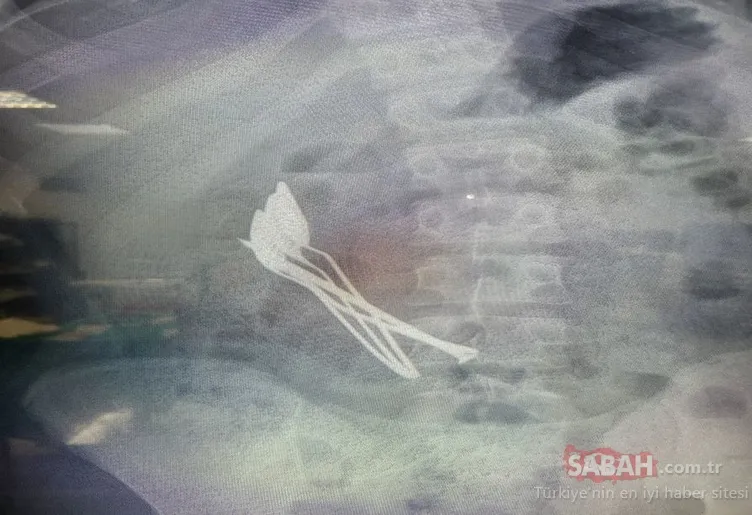

Kayseri Şehir Hastanesi’nde yapılan incelemede çocuğun midesinde 4 metal tatlı kaşığı ve 1 çivi görüldü.

Kayseri Şehir Hastanesi Çocuk Cerrahisi ve Ürolojisi Anabilim Dalı Başkanı Doç. Dr. Mustafa Erman Dörterler ve ekibi tarafından yaklaşık 2 saat süren operasyonda çocuğun midesindeki kaşıklar ve çivi çıkarıldı.